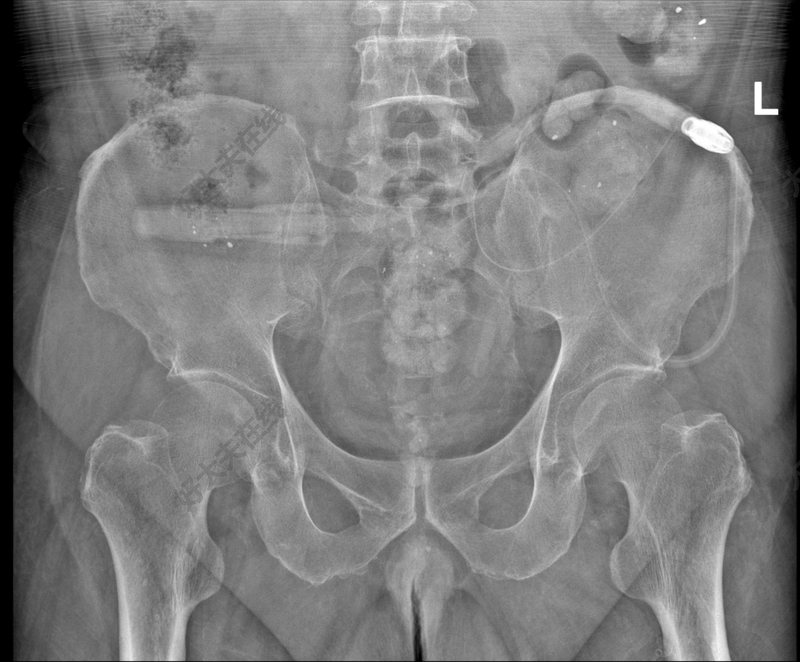

腹膜透析腹透管漂管

治疗前丹东来患者杜xx,腹膜透析1年余。腹透超滤量为负400至750ml每天,伴浮肿,高血压,气短。术前x光提示腹透管漂管。治疗中中国医科大学附属第一医院肾内科及腹透中心朱新旺医生,采用不开刀,无创式,介入复位技术,将腹透管复位。治疗后治疗后7天腹透管复位成功,超滤正常,浮肿缓解。

治疗前肥胖患者,腹膜透析置管术后2个月。超滤困难,浮肿加重。查盆腔X光提示腹透管漂管。治疗中中国医科大学附属第一医院肾内科腹透中心朱新旺医生,不开刀不手术,利用导丝无创复位漂管的腹透管。治疗后治疗后7天患者恢复正常腹透。超滤量500到700ml每天,浮肿消退。